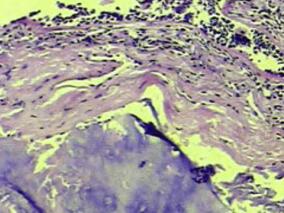

1小时条评论一、病史摘要 患者,男性,39岁,农民。因反复咯血3年,再发加重3周于2008年11月17日入院。患者自诉于3年前无明显诱因出现间断咯血,量不多,一日约10ml左右,鲜红色,伴干咳,胸痛,气促,无发热、盗汗、体重减轻等。2006年9月无明显诱因出现咯鲜血,一次约500ml。...